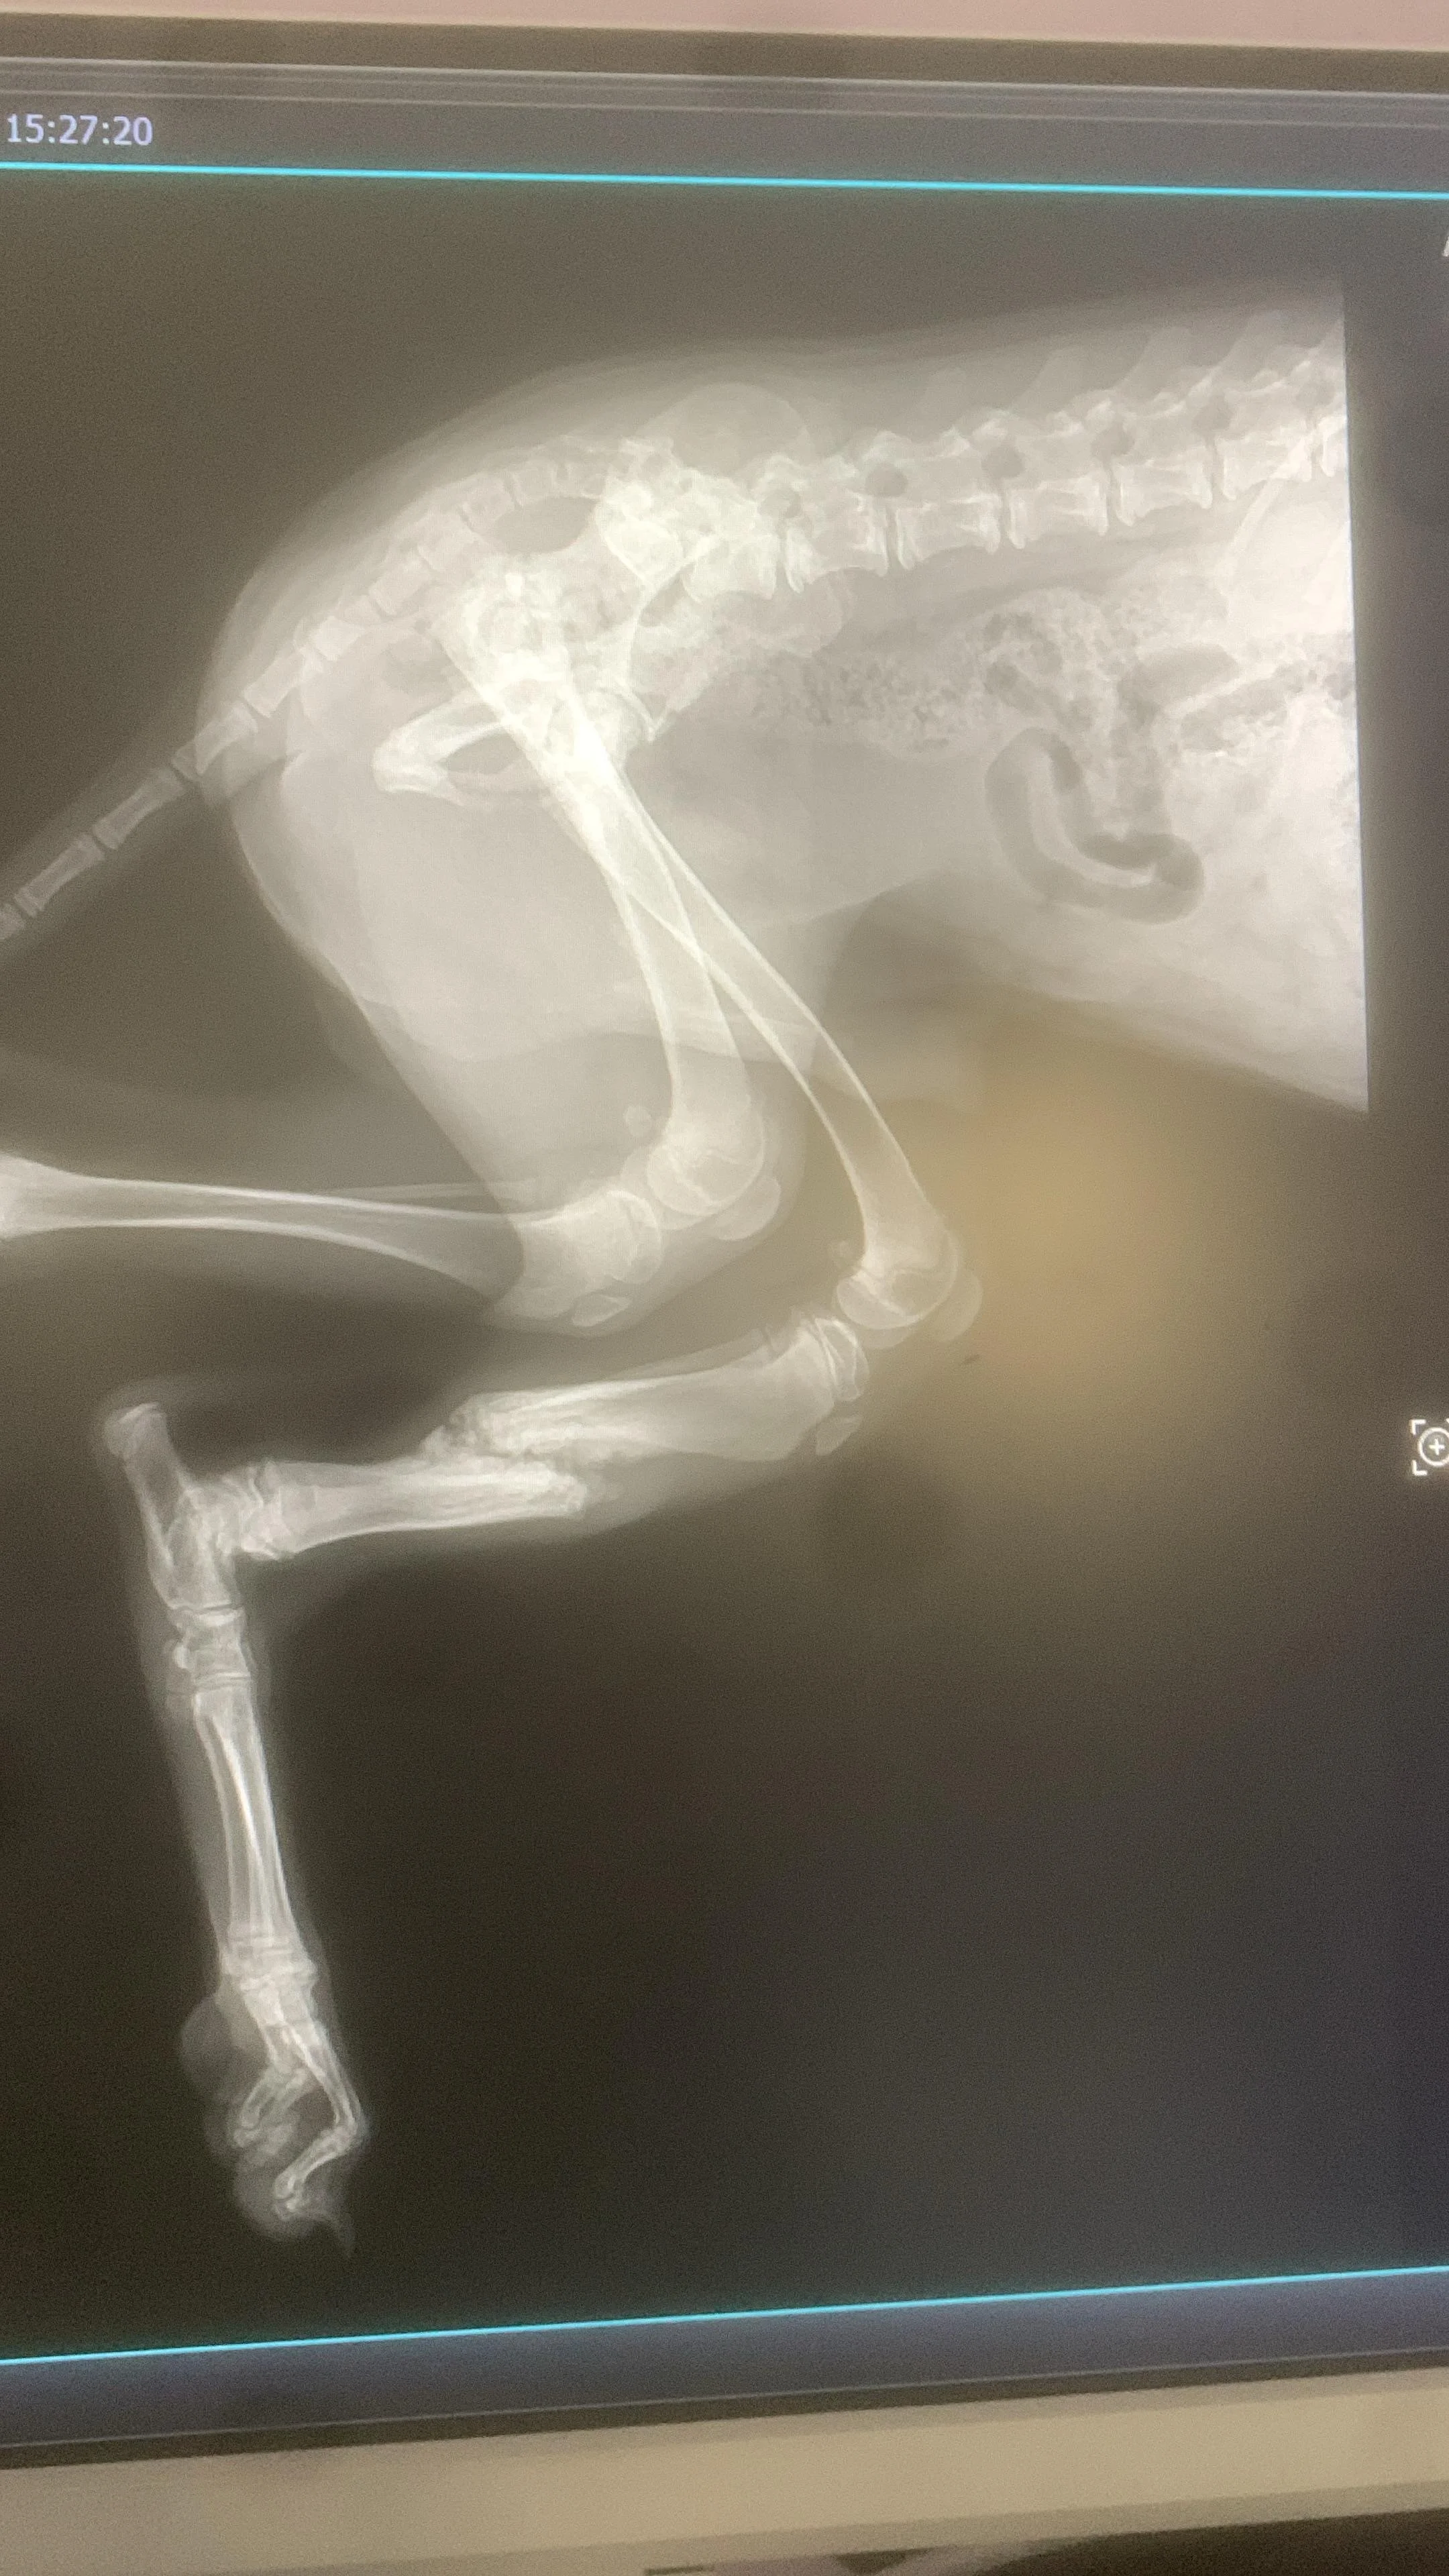

Nach einem zweiten Röntgen erklärte dieser Tierarzt, dass der Bruch von selbst verheilt sei.